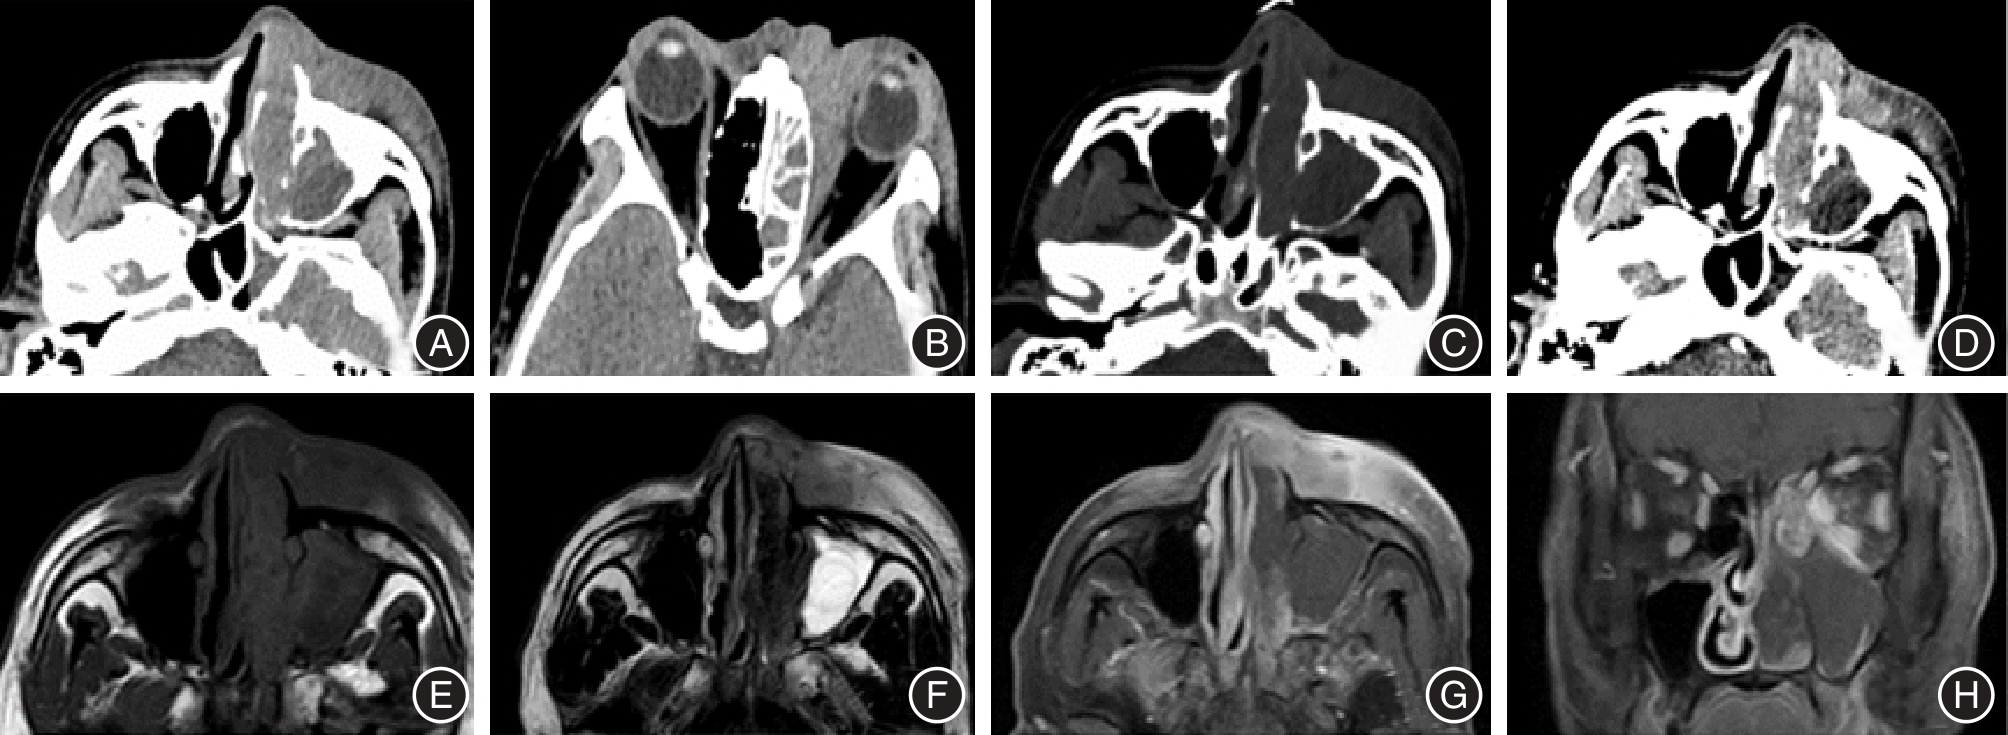

目的 探讨鼻腔鼻窦鳞状细胞癌(SCC)和淋巴瘤(NHL)的增强CT和MRI影像特征,分析不同影像特征鉴别鼻腔鼻窦SCC与NHL的效能。 方法 回顾性分析行鼻窦增强CT和增强MRI检查并经手术病理证实的67例鼻腔鼻窦SCC及NHL患者的影像学及临床、病理资料,分析肿瘤起源部位、最大径、CT密度、MRI信号强度、增强强化程度、肿瘤内部坏死、邻近骨质破坏、对周围组织的侵犯、扫描范围内颈部淋巴结转移情况等影像特征,采用受试者操作特征(ROC)曲线及曲线下面积(AUC)分析不同影像学特征鉴别鼻腔鼻窦SCC和NHL的效能。 结果 鼻腔鼻窦SCC与NHL的肿瘤起源部位、最大径、肿瘤内部坏死、周围骨质破坏以及周围组织侵犯5个影像学特征组间差异有统计学意义(P < 0.05),鉴别SCC与NHL的AUC分别为0.708、0.694、0.785、0.850、0.629。联合肿瘤起源部位、肿瘤内部坏死、周围骨质破坏3个影像特征鉴别SCC与NHL的AUC为0.969,灵敏度及特异度分别为83.9%及97.2%。 结论 肿瘤起源部位、最大径、肿瘤内部坏死、骨质破坏及周围组织侵犯的增强CT及MRI影像征象有助于鼻腔鼻窦SCC与NHL的鉴别,尤其是出现肿瘤起源于鼻腔、坏死少见、骨质破坏轻微,应优先考虑鼻腔鼻窦NHL的可能。增强CT和MRI有助于鼻腔鼻窦SCC与NHL的鉴别,联合使用有助于提高鉴别诊断效能。